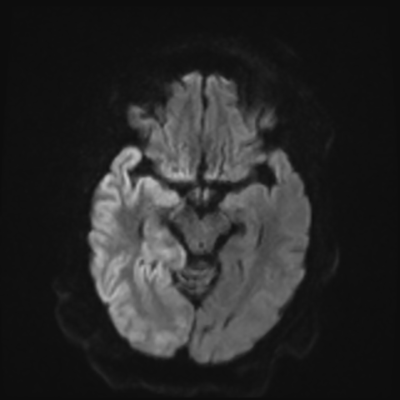

You come back the next day and see how things are going. The patient's electrographic record has shown a moderate encephalopathy (diffuse slowing, disorganization) with frequent right posterior quadrant delta slowing. Based on this result, and an adequately improved clinical examination, you give the okay to proceed with obtaining an MRI of his brain. This is shown below.

MRI brain (DWI)